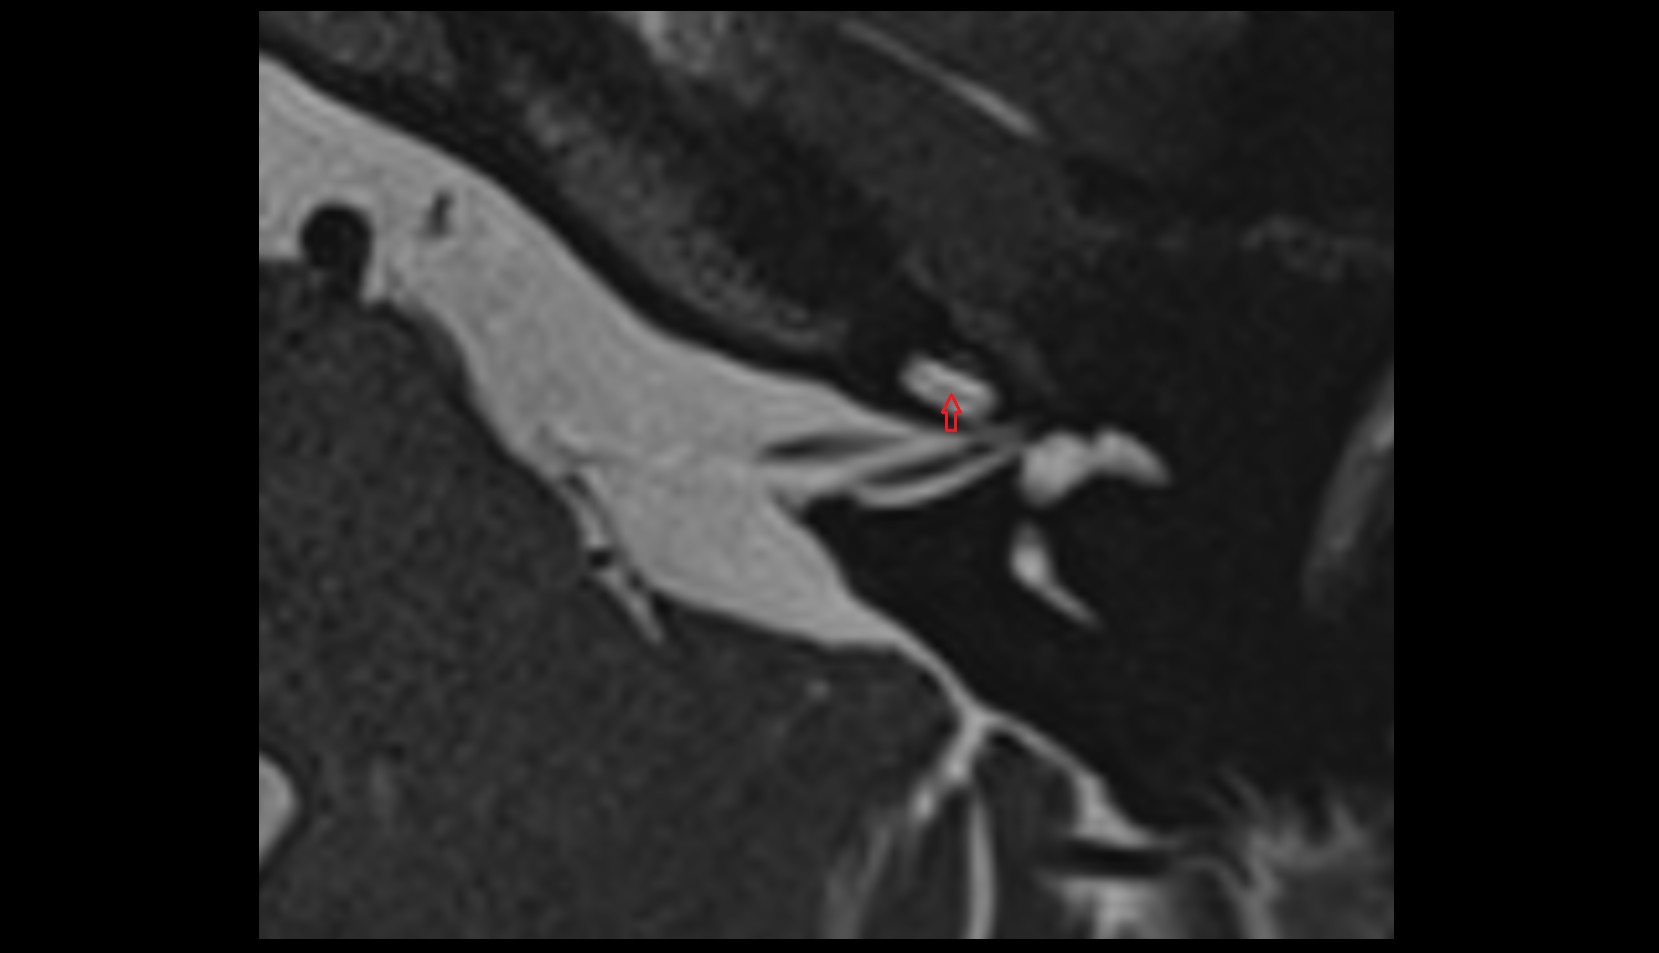

- Right coronary artery (RCA)